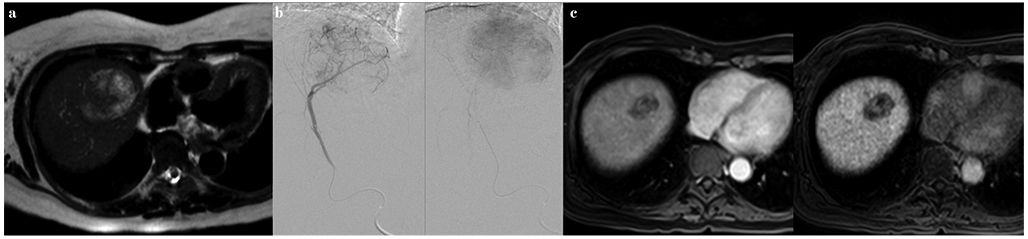

Ablaţia prin radiofrecvenţă reprezintă standardul de tratament pentru pacienţii cu carcinom hepatocelular în stadiu BCLC 0 și A, nerezecabil chirurgical. Ablaţia termică a unui nodul tumoral cu dimensiuni de 2-3 cm reprezintă o alternativă la rezecţia chirurgicală la pacienţii corect selecţionaţi (fig. 3).

VM 25, p.12-13 - 3

Fig. 3 - a) Examinarea RM cu evidenţierea unui nodul tumoral în segmentul II-III cu caractere tipice de hepatocarcinom; b) evaluare CT la 3 luni post-ablaţie cu radiofrecvenţă, cu necroza completă a leziunii tumorale.